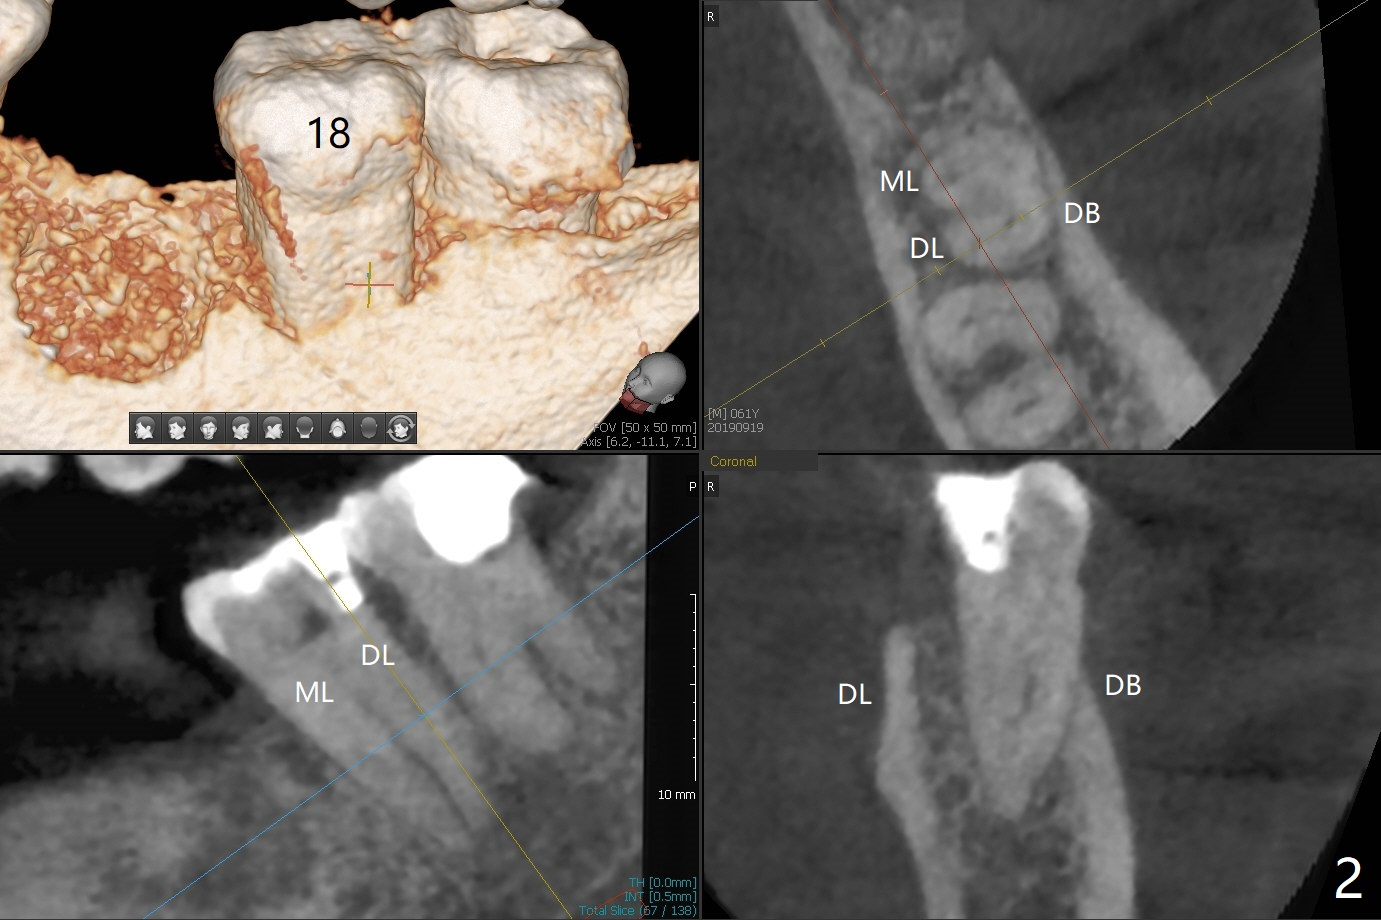

A 61-year-old man may have referral pain between #17 and 18. The canals at #18 are narrower than those at #17 (Fig.1-3). If #18 needs RCT, blocks should be removed (Fig.4-6 vs. 4'-6').